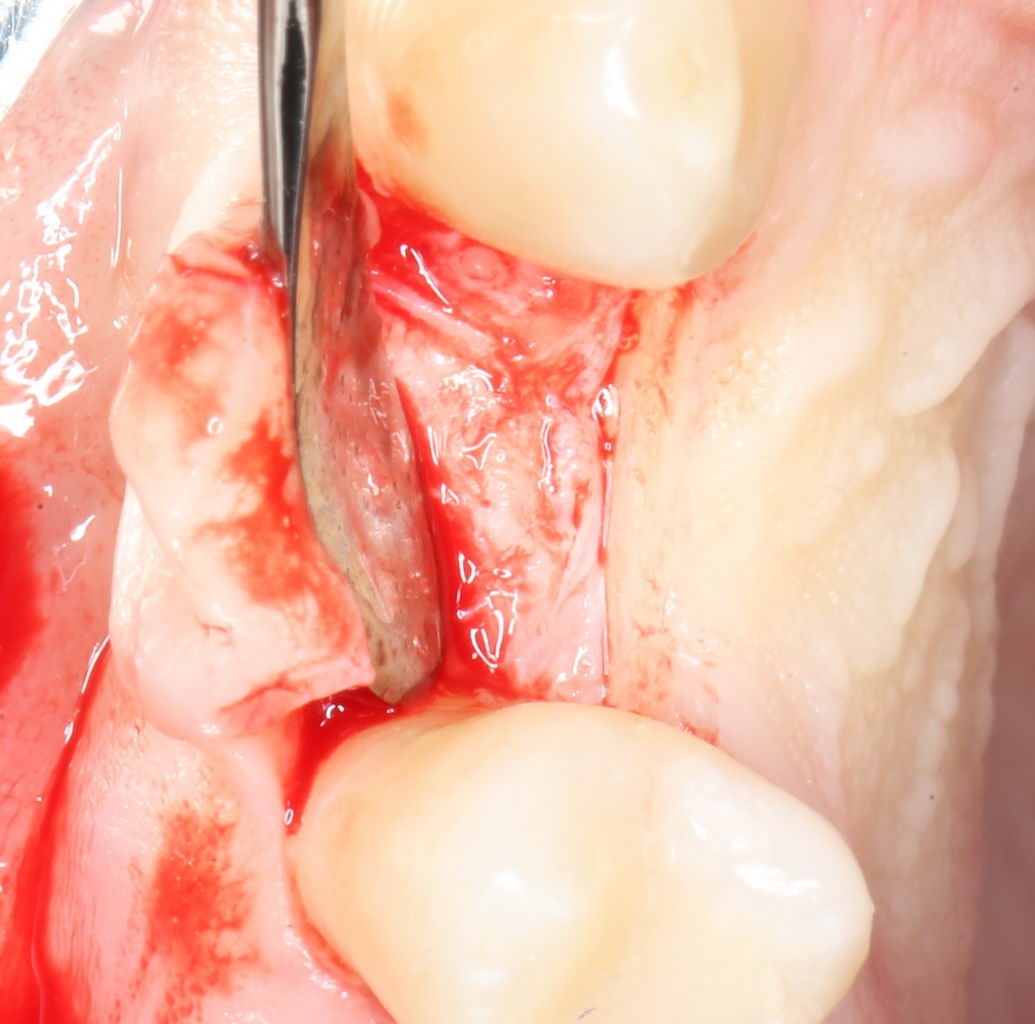

Разрез и скелетирование альвеолярного гребня.

Разрез и скелетирование делаются, исходя из двух взаимоисключающих нюансов: с одной стороны, разрез должен быть минимально травматичным, с другой — обеспечивать хороший обзор:

Мы немного смещаем разрез в сторону нёба для того, чтобы потом нормально сформировать десну. Это видно на правой фотографии выше.

Затем рана скелетируется, открывается кость верхней челюсти: